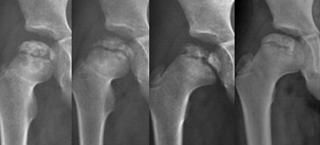

2005.07.04 2005.11.07 2006.10.02 2008.07.28

患者,邵XX,男,江苏宿豫,05年3月(5岁)从高处坠落,4个月后出现右髋疼痛、跛行,当地诊断为股骨头坏死,行股骨头减压术等,无效;06年9月到北亚骨科医院,以股骨头坏死晚期(Ⅱ型)入院,经北亚量子整体医学“三补一活”整体医学治疗,22个月(住院14天)复查,临床治愈,功能恢复正常。